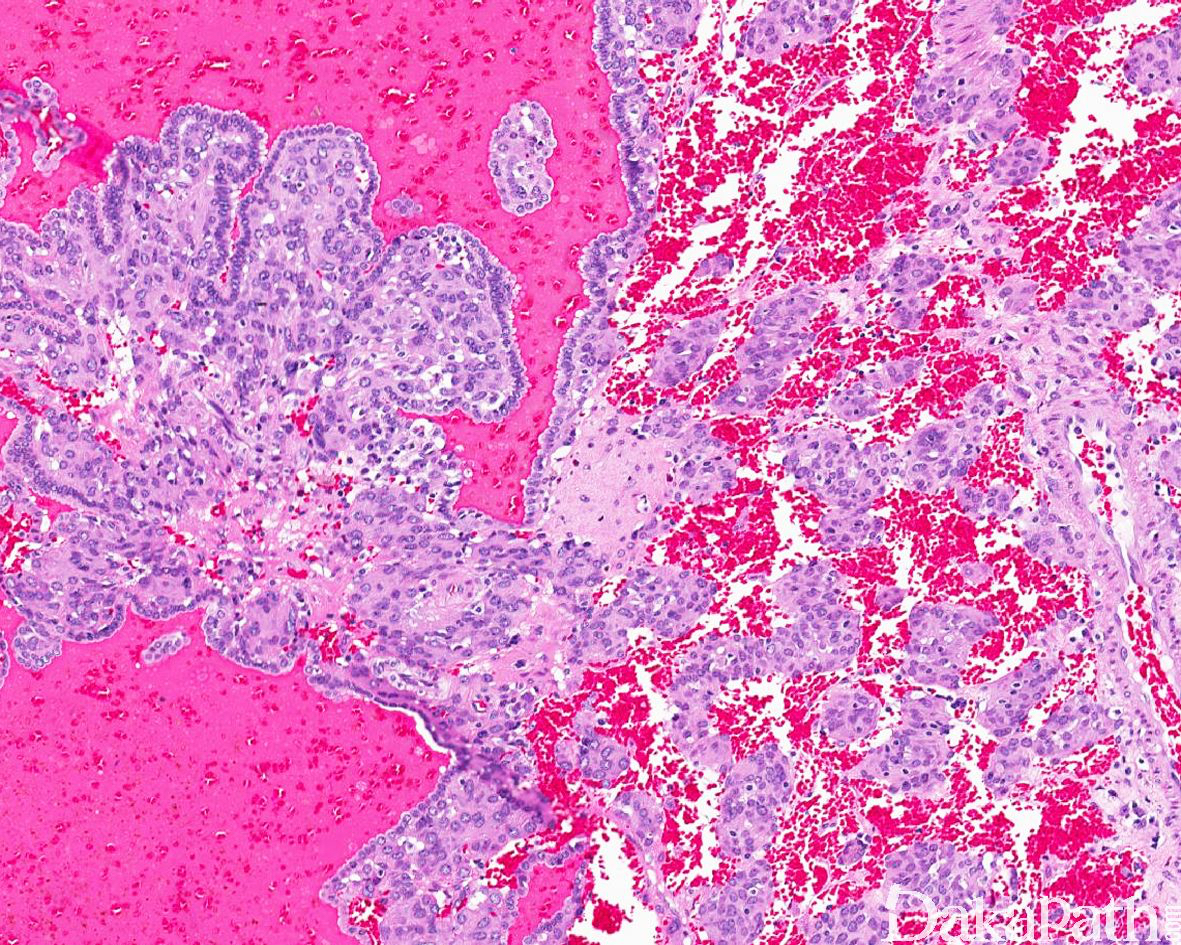

瘤细胞呈实性片状或围绕分支状血管呈血管外皮瘤样排列,常见间质水肿导致的微囊状结构,肿瘤周边可见瘤细胞围绕内陷的肾小管呈乳头状排列。